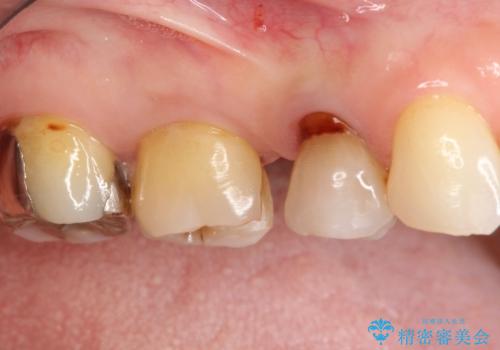

- 以前詰めた、インレーが外れたことを主訴に来院されました。

隣の歯にも虫歯を認めたためまとめて治療を行いました。

辺縁隆線にクラックラインを認め、破折防止のためにクラウンによる治療を希望されました。